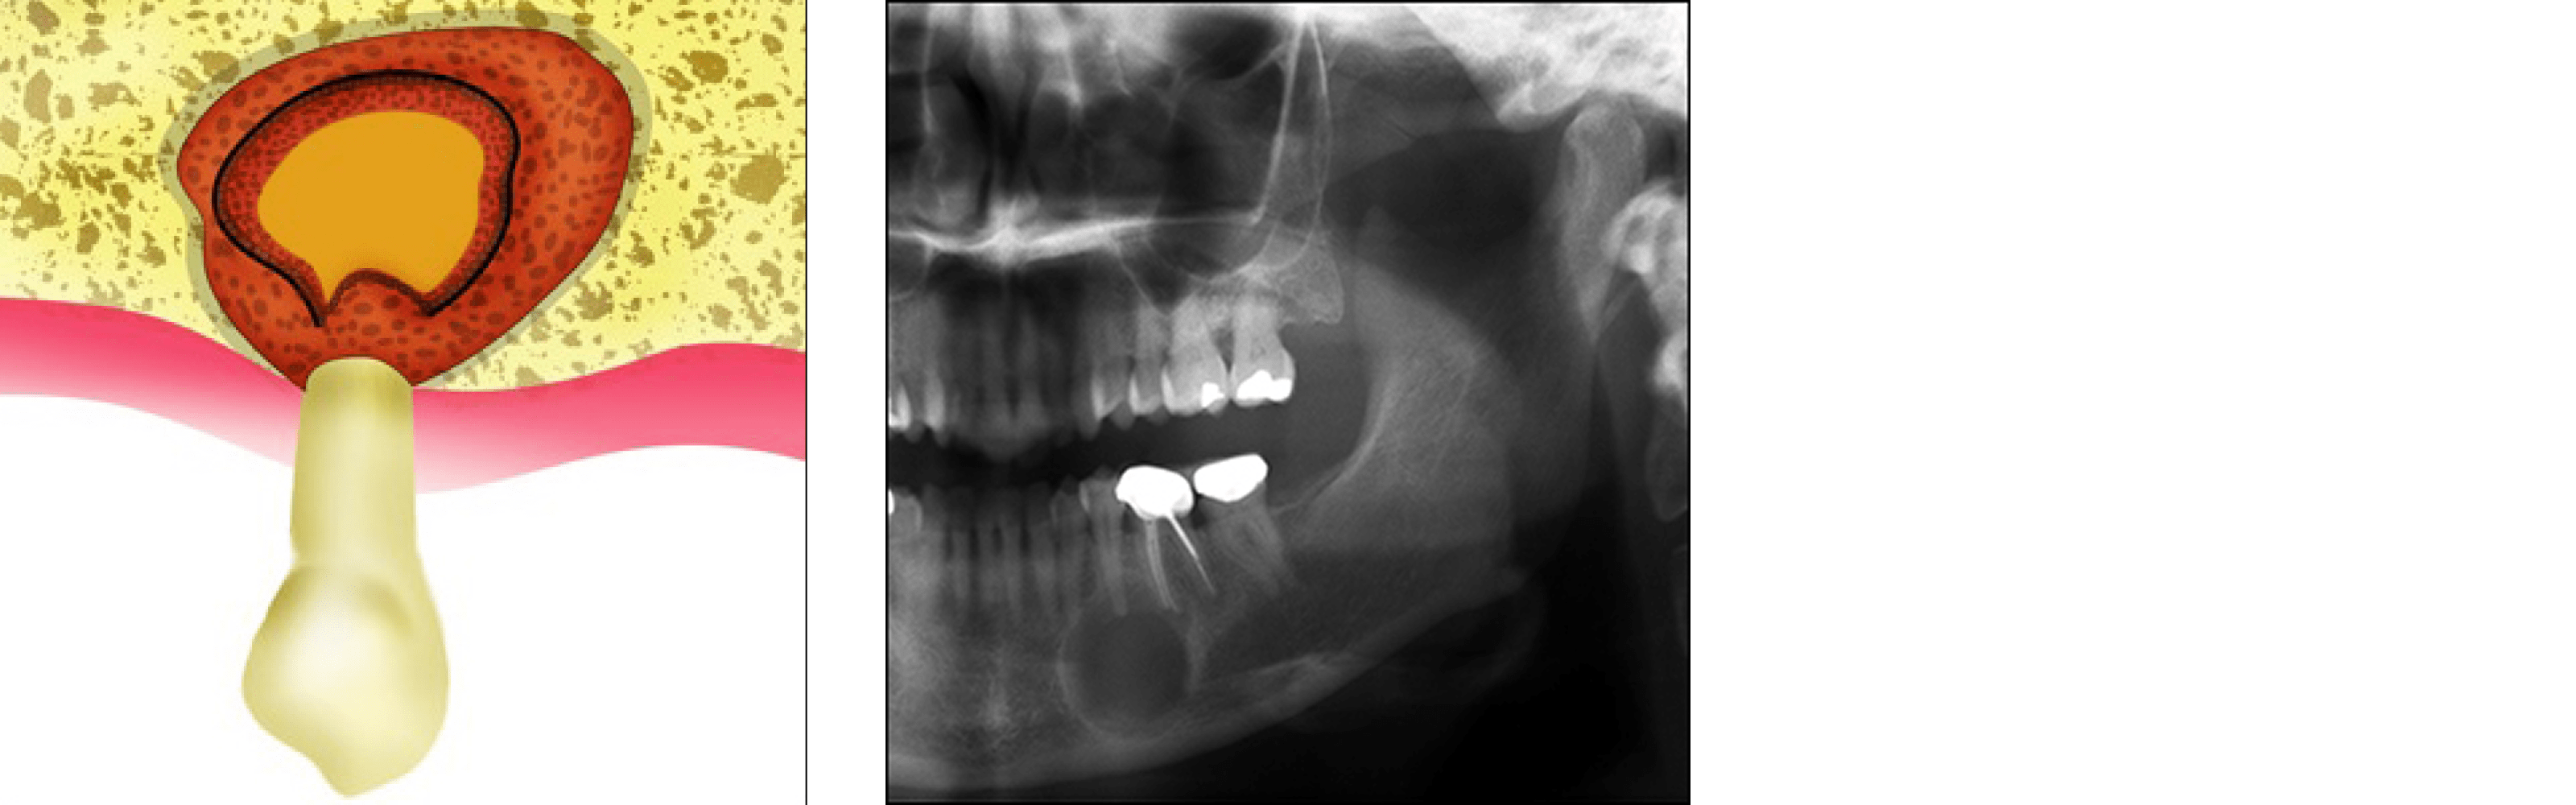

Apicoectomy (Periapical Surgery)

Generally, a root canal is all that is need to salvage a tooth from being extracted. Occasionally there may be a point in which the root canal treatment will not be sufficient enough to heal the tooth and your primary dentist may recommend apical surgery or root-end surgery.

What is an apicoectomy?

An apicoectomy, root-end resection or periapical surgery, is the removal of the root tip and the surrounding infected tissue of an abscessed tooth. This procedure may be necessary when inflammation and infection persists in the area around the root tip after root canal therapy.

When to call a professional?

If you are having any pain or swelling from a tooth that has had root-canal treatment, contact your dentist. Sometimes after a root canal a pimple develops near the tooth. This pimple will often go away and then come back, this is called a fistula. You may notice pus draining from the fistula. The fistula is a sign that there is an infection and your body is draining it out through the pimple. There is usually no pain in this situation, but you may notice a bad taste or odor in your mouth.

How is the surgery done?

The oral surgeon will make a small incision (cut) in your gum and lift the gum away from the tooth and bone. The infected tissue will be removed along with the last few millimeters of the root tip.

To complete the apicoectomy, the surgeon will clean and seal the end of the tooth's canal. The cleaning usually is done under a special microscope using ultrasonic instruments. The light and magnification allow the surgeon to see the area clearly. This increases the chance that the procedure will succeed. Then an X-ray of the area is taken before stitching the tissue back in place.

Most apicoectomies take 45 to 60 minutes. The length will depend on the location of the tooth and the complexity of the root structure. Procedures on front teeth are generally the shortest. Those on lower molars generally take the longest.